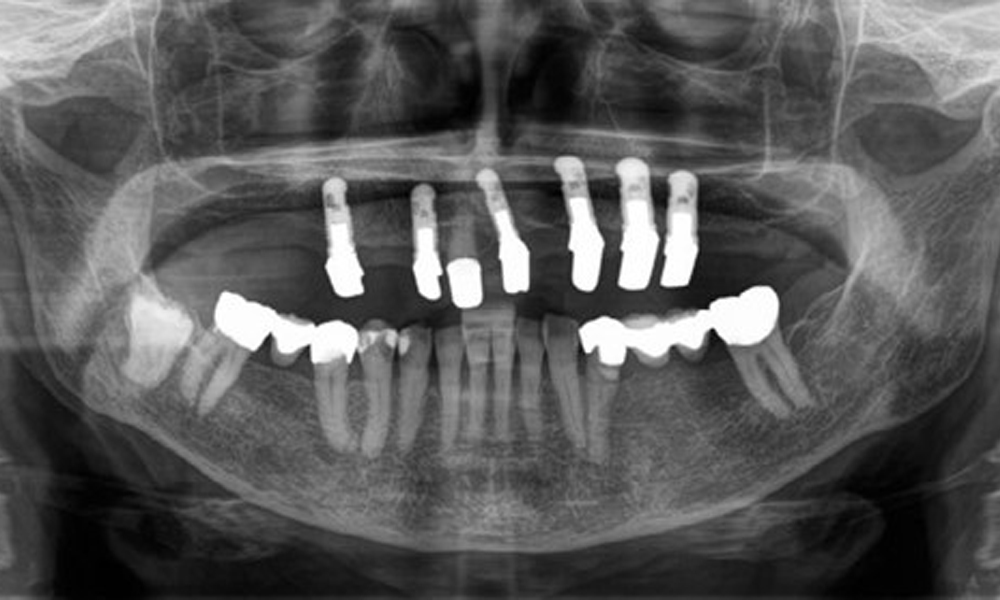

The patient was fitted with a combined removable maxillary telescopic prosthesis more than 25 years ago (Fig. 1, Fig. 2, Fig. 3) and is very happy with her dentures. The patient has an adequate fixed denture for the mandible (Fig. 4).

The dental findings are as follows: Combined removable implant and tooth-supported telescopic prostheses on implants 15, 13, 21, 23, 24, 25 and tooth 11 (Fig. 1, Fig. 2, Fig. 3). The patient was fitted with a fixed mandibular denture. Adequate bridges were present over 37 to 34 and 45 to 47 (Fig. 4), the crown margins were intact and there were no active caries. A composite filling with a marginal gap was present on tooth 43. There was mandibular gingival recession, exposing 1 to 3 mm of root surface. This also applies to 11.

Radiological findings

The radiological findings show partially edentulous dentition with maxillary implants for teeth 15, 13, 21, 23, 24, 25 and a telescopic crown on tooth 11. Adequate mandibular bridges spanning 37 to 34 and 45 to 47 are present. 48 is impacted. There are suspected secondary caries distally on 43 and mesially on 44. 44 is restored with a non-radiopaque cavity lining. There is generalised horizontal bone loss of approx. 10% to 30% and localised vertical bone loss affecting teeth 22 and 42 (Fig. 5).